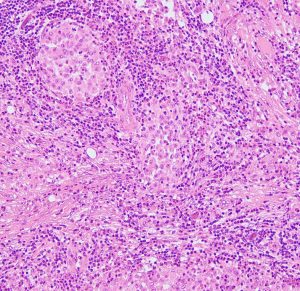

LCHの病理像

頭蓋骨のLCHの病理像です。左はHE染色,右はランゲルハンス細胞に特異性の高いCD1a(specific to dendric Langerhans cells) 染色です。多数のLangerhans cellとともに,組織球,リンパ球,好酸球,多核細胞など多彩な細胞浸潤があります。これは活動性のLCHの病巣から摘出したものです。

自然緩解して収まった病巣を生検術で摘出しても,このような典型的な病理像がなくて慢性炎症像がみられるだけのことがあります。その場合は確定診断がつきません。

左は,活動性の病巣です。右は,活動期が終わり慢性炎症所見を伴いながら肉芽種に移行する過程です。

別な例の病理像です

左はHEで血管周囲に多様な細胞浸潤像があります,右はS-100です